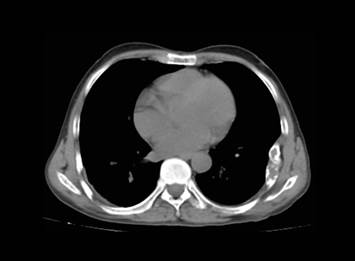

La radiografía de tórax (figura 1) mostró lesión expansiva en porción media de arco de 6° y 7° costillas izquierdas, sin lesiones parenquimales. Incidentalmente se observó una lesión quística en tercio distal de diáfisis humeral izquierda, la misma que se aprecia mejor en ventana mediastínica de una TEM de tórax (figura 2).